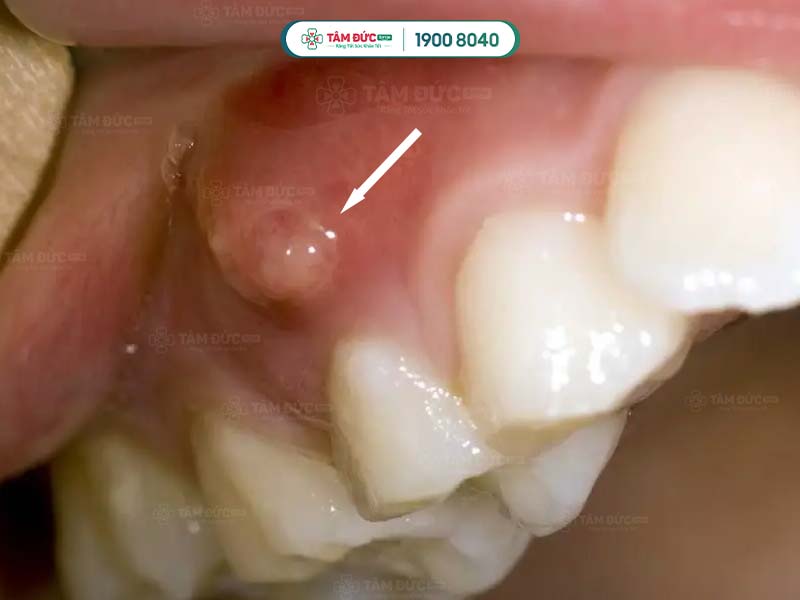

Nướu răng hàm trên bị sưng và tụ mủ

- Áp xe răng: Đây là bệnh nhiễm trùng nghiêm trọng ở chân răng, có thể gây sưng, đỏ, đau nhức dữ dội, sốt, thậm chí là sưng mặt.